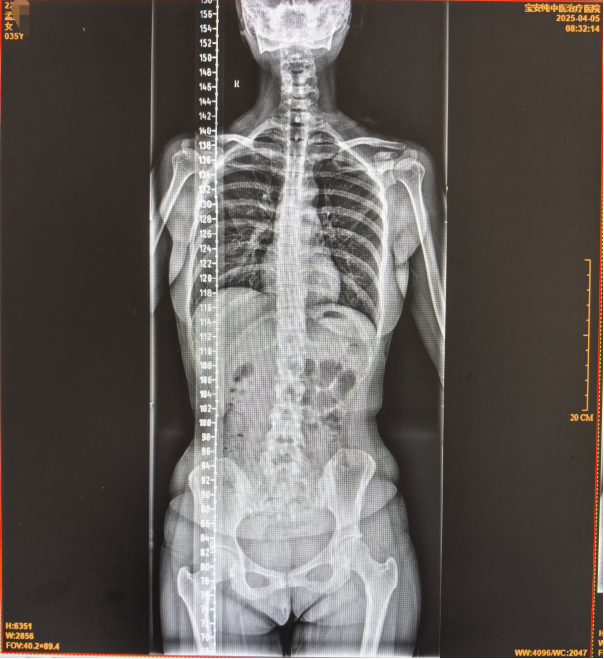

4月05日治疗多次后复查片子: